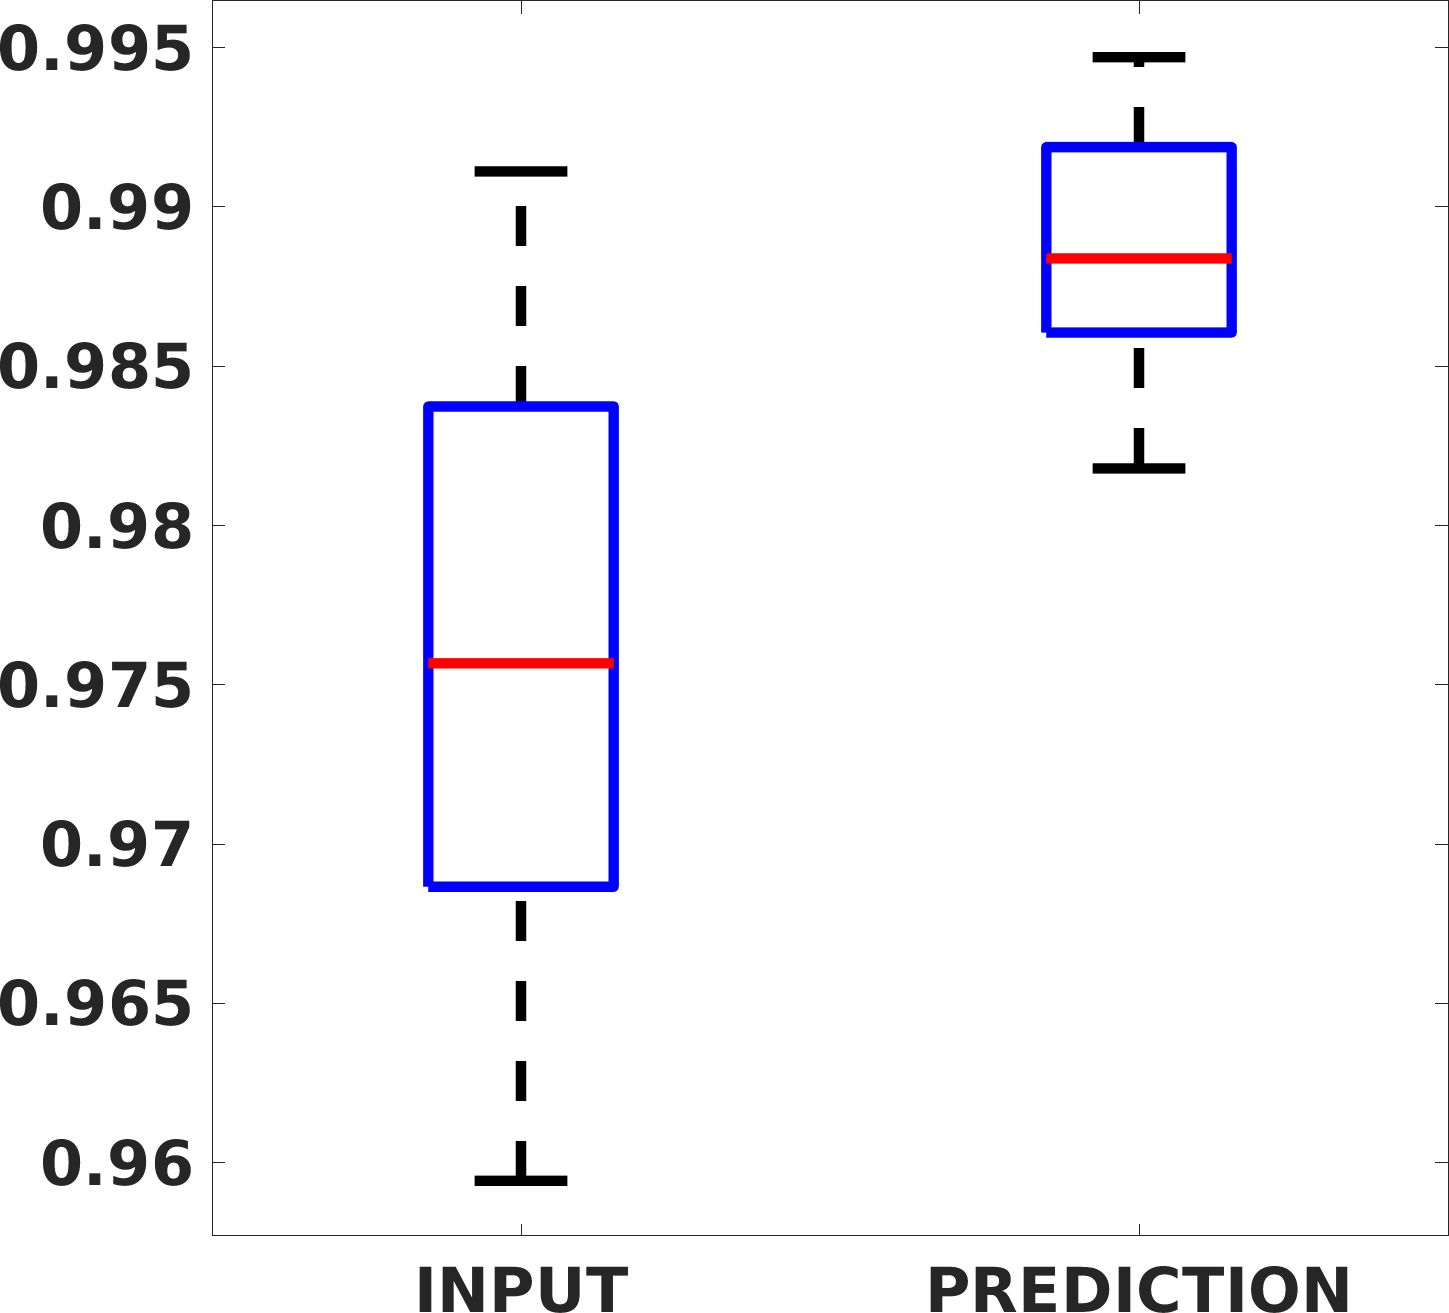

Fig. 8 shows the box plot of the SSIM (a-b-c, left) and MAE (a-b-c, right) quantitative metrics, as performed for PSNR metric. Also, these metrics show that our method improves the results of Cubic convolution both in terms of average value and variability. For example, the SSIM median value improves of on obstetric 4X images and the MAE median value improves of on cardiac 2X images.

Fig. 17 (left) shows the box plot of the quantitative metrics, comparing the target images with the prediction and the Cubic convolution, respectively. The PSNR metric is computed on a data set of 200 images, belonging to the same district, and with the same up-sampling factor. Analysing the obstetric anatomical district and concerning the corresponding raw images (Fig. 7 (a, left)), the denoising allows the network to significantly improve the results of the up-sampling and the prediction. In particular, comparing the target images with the predicted images, the median PSNR value of obstetric 2X denoised images is 51.8, compared to the median PSNR value of obstetric 2X raw images which is 36.9.

Fig. 17 (right) shows the histogram of the absolute value of the error with respect to the target, of the prediction and Cubic convolution respectively. This result shows that our framework increase of and (2X and 4X, respectively) the number of pixels where the prediction error is lower than 5, which is very similar to the target when visually analysing the images, and improved with respect to the learning framework applied to raw images. According to Fig. 18, our method improves the accuracy of Cubic convolution. For example, the SSIM increases of on cardiac 2X and the MAE increases of on abdominal 4X.